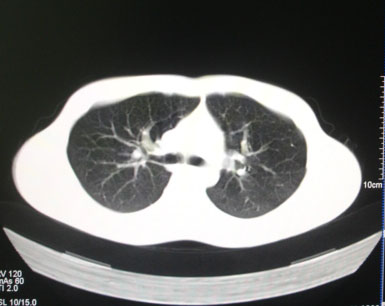

标题: CT26938:单发肺窗

病人17岁。咳嗽伴血丝痰2年?外院x片示左上肺椭圆形影,疑胸腺瘤

左肺尖见占位,建议上传纵隔窗及向上扫描。

左上纵隔占位性病变?